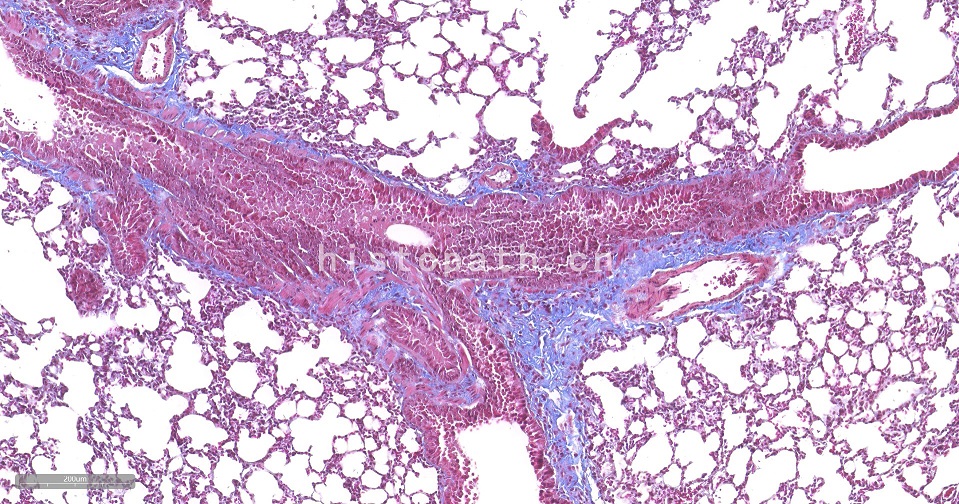

Masson染色原理:

Masson 三色染色又称马松染色,是结缔组织染色中最经典的一种方法,是胶原纤维染色权威而经典的技术方法。所谓三色染色通常是指染胞核和能选择性的显示胶原纤维和肌纤维。该法染色原理与阴离子染料分子的大小和组织的渗透有关:分子的大小由分子量来体现,小分子量易穿透结构致密、渗透性低的组织,而大分子量则只能进入结构疏松的、渗透性高的组织。然而,淡绿或苯胺蓝的分子量很大,因此 Masson 染色后肌纤维呈红色, 胶原纤维呈绿色或蓝色,主要用于区分胶原纤维和肌纤维。

染色结果:胶原纤维、黏液、软骨呈蓝色(如亮绿液染色为绿色),胞质、肌肉、纤维素、神经胶质呈红色,胞核黑蓝色。